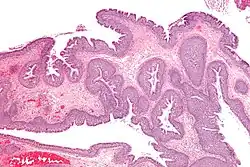

Polipy nosa – powstają w wyniku zmian zapalnych lub alergicznych błony śluzowej nosa. Najczęściej wychodzą ze środkowego przewodu nosowego, zatok szczękowych lub sitowych. Tworzenie polipa rozpoczyna się od obrzęku błony śluzowej, rozrostu tkanki podśluzowej, gromadzenia się płynu i tworzeniem się szypuły poprzez grawitacyjne opadanie naciągniętego zdwojenia błony śluzowej wypełnionego płynem.